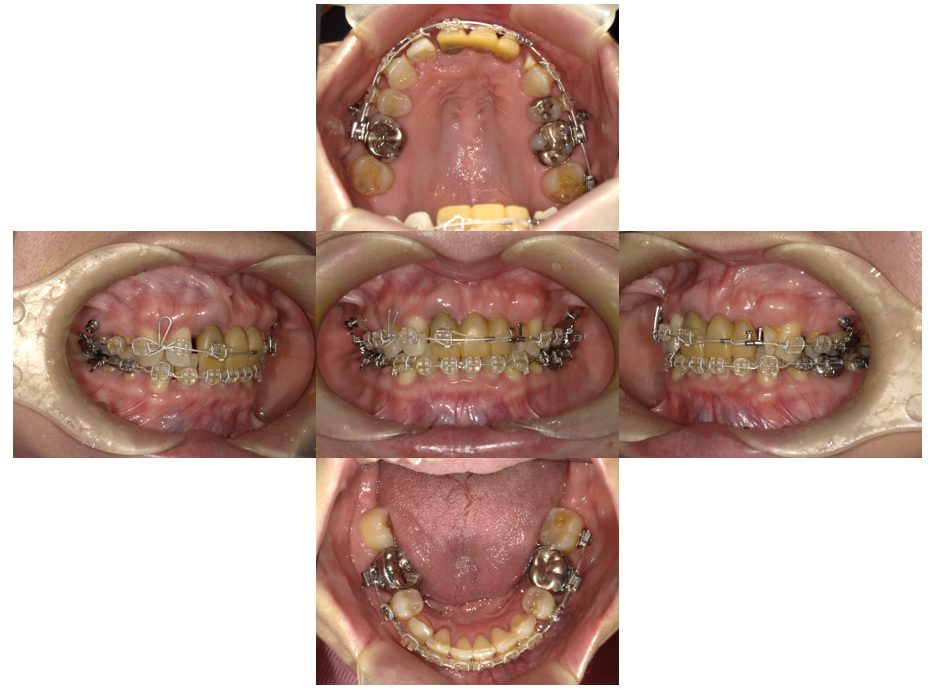

外科矯正治療・インプラント治療の症例紹介(三隅歯科クリニック)

三隅 賢祐(三隅歯科クリニック)

症例詳細

| 主訴 | 20代女性 矯正治療希望。治療途中の歯もあるので治したい。左顎関節が痛い。 |

| 治療内容 | 矯正治療を行いました。 |

| 治療費 | 1,400,000円(税込み) |

| 治療期間 | 3年(矯正治療期間 2年半) |

| 治療回数 | 40回 |

| 想定されたリスク | 顎骨の変形があったので、全身麻酔下による外科処置が必要になり、身体的、精神的負担が増す可能性がありました。 清掃状況によっては矯正中にむし歯が発生するリスクがありました。 |